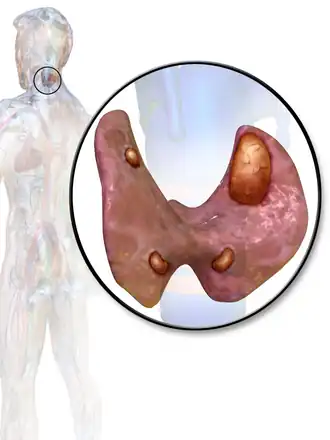

Um ser humano normalmente tem quatro glândulas paratireoides, localizadas por atrás da tireóide, no pescoço. A paratireoide secreta hormônio da paratireóide (PTH), que aumenta a concentração de cálcio no sangue (calcemia), ao induzir a liberação de cálcio dos ossos para o sangue e ao induzir os rins a reabsorverem o cálcio para evitar sua excreção. Quando um adenoma de paratireoide causa hiperparatiroidismo, mais hormônio da paratireóide é secretada, causando uma concentração elevada de cálcio no sangue (hipercalcemia).[2]

Antes da cirurgia o tumor deve ser localizado. Apesar das glândulas paratireoides estarem normalmente localizadas atrás das tireoides, algumas pessoas têm uma ou mais glândulas paratireoides, em outros lugares do pescoço ou no peito. Cerca de 10% dos adenomas de paratireoide são ectópicos.[6] Portanto diversas técnicas de imagem são utilizadas, tais como o sestamibi, SPECT, ultra-som, ressonância magnética, e TC.[7].